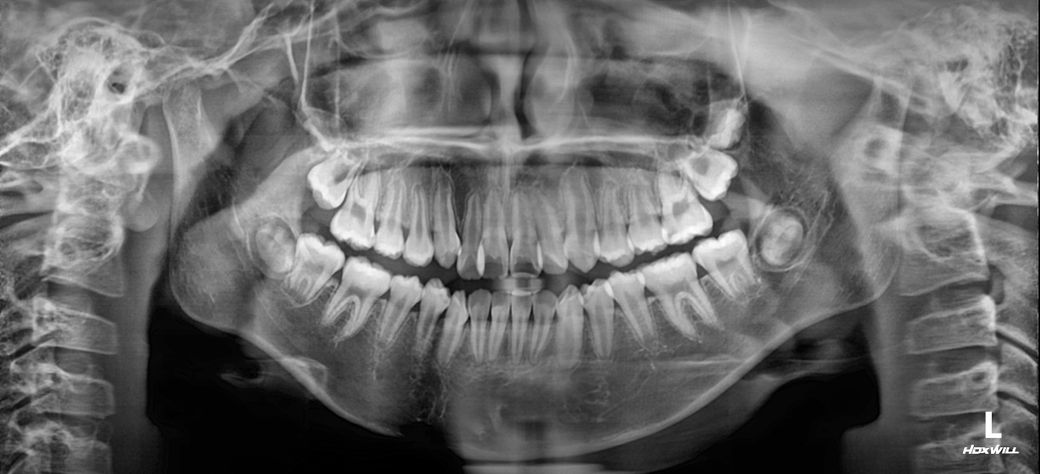

중1 여자 아이 교정진단 부탁드립니다.

앵글씨 몇급인지 궁금합니다.

의사 선생님마다 소견이 다르셔서 혼란 스럽네요.중1 여자 아이구요.시기적으로 지금 교정을 시작하기에 적절한지 궁금합니다.

앵글 2급 부정교합이며, 지금 교정하는 것이 좋을 것으로 보입니다. 더 늦어지면 교정이 까다로워 질 수도 있습니다. 지금 현재도 쉬운 케이스는 아닙니다.

앵글씨 부정교합측면에서 보면 1급인거 같고 치열이 좋지 않아서 중학교 1학년이면 교정을 시작하셔도 괜찮을 시기인거 같습니다.